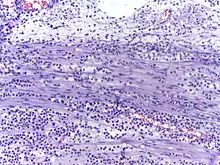

![]() | Fibroblasts | Fibroblasts in intestinal pneumonia | Category: Fibroblasts | Fibroblast |